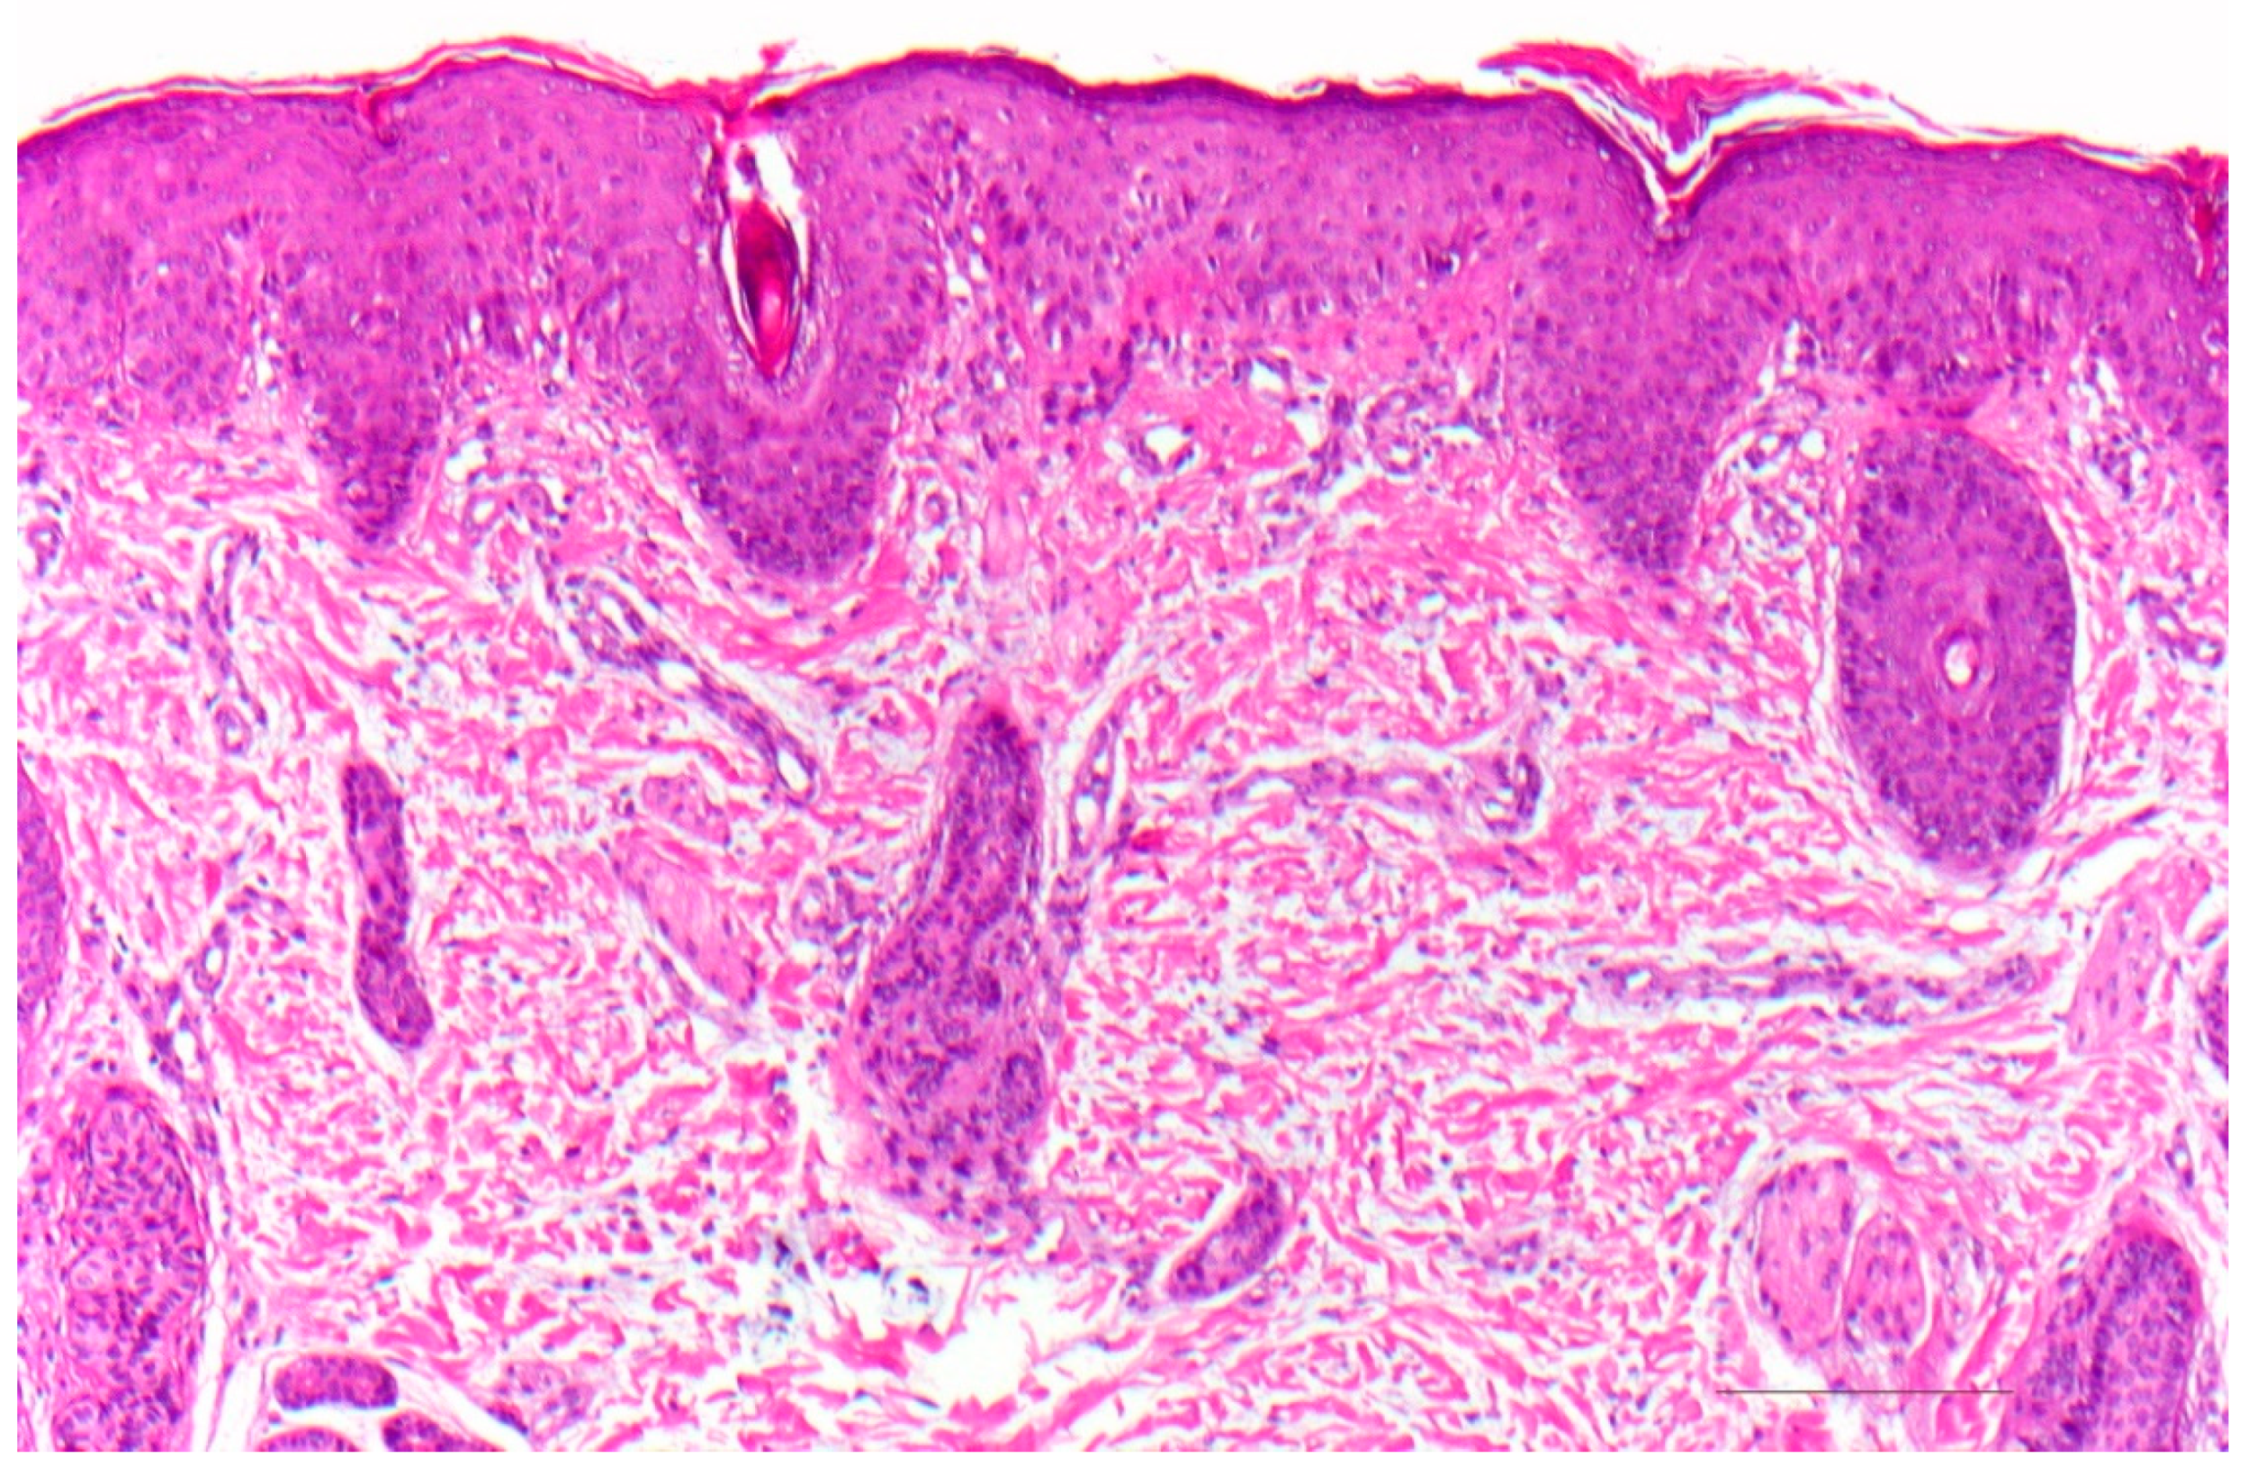

3. Ichthyosis Vulgaris

3.1. Histology